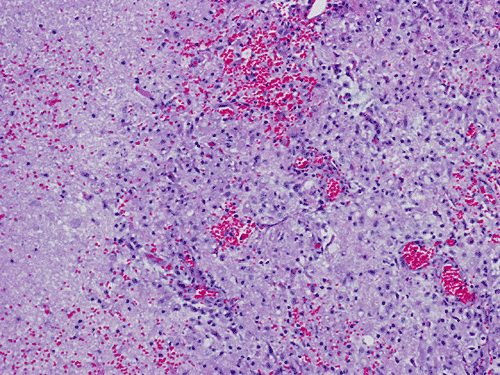

He was admitted again. In this admission, he developed left intraparenchymal hemorrhage associated with the enhancing mass, edema, and 0.4 cm left to right midline shift. A craniectomy was performed to evacuate the blood and biopsy the enhancing mass. The followings are representative images from the biopsy material.

Panel A to E are intra-operative cytologic preparation, Panel E to J are frozen section, Panel K to N are permanent sections.